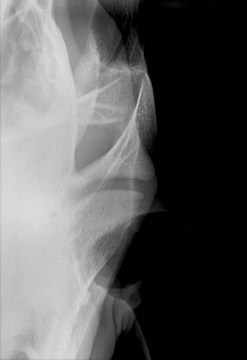

Temporomandibular articulation

Despite its superficial location, traumatic injuries to the temporomandibular joint are rare. On occasion, an open wound is encountered with direct communication to the joint; these cases are typically presented for treatment some time after initial injury, usually due to non-healing of the wound. Thorough assessment of the injury using skyline radiographic projections3 (Fig. 9.16; or preferably by computed tomography if available) and ultrasonography is essential when planning treatment. Debridement of the wound and lavage of the joint are performed under general anesthesia and aided by arthroscopy, followed by post-surgical wound management and antibiotic therapy. This usually results in successful resolution of the articular sepsis; however, some masticatory dysfunction may be a long-term sequel. Mandibular condylectomy and meniscectomy with a successful outcome have also been described and are an option for cases with severe or longstanding injury.4 Further details of temporomandibular disease are presented in Chapter 23.

image

Fig. 9.16 Radiographic projection to highlight the temporomandibular joint.